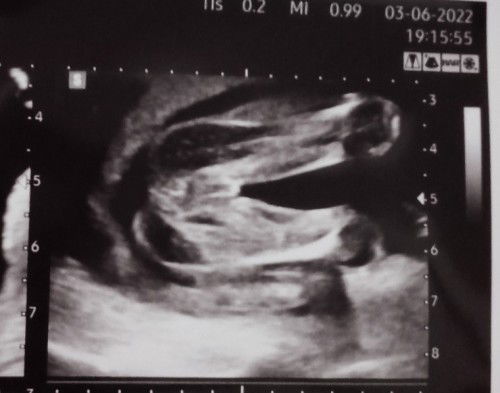

แม่ๆคิดว่าผู้หญิงชัดไหมคะ

คุณหมอว่าระหว่างขาน้องไม่เห็นกะจู๋น่าจะผู้หญิงส่วนตัวก็ดีใจมากเลยมีใครเห็นว่าผู้ชายไหมคะ หรือหญิงชัดๆ😂😂#ขอบคุณสำหรับคำตอบค่ะ

น่าจะผญชัวร์ๆเลยจ้าแม่ บ้านนี้ก็ซาวด์ออกมาเป็นแบบนี้ เดี๋ยวรอดูตอนคลอดอีกทีจะมีจู๋โผล่มามั้ย🤣

ออค่ะ.น่าจะญน่ะค่ะ